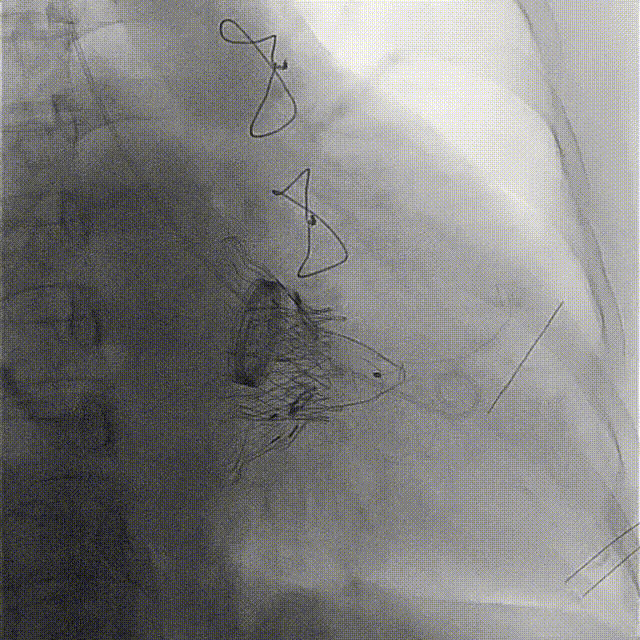

術前DSA

手術在全麻狀態下開展,海軍軍醫大學附屬長海醫院陸方林教授與廈門心血管病醫院王焱院長共同上臺,為患者進行手術。此次手術采用經右側頸靜脈入路的方式將輸送器送入患者心臟內,在TEE及DSA引導下調整輸送器頭端角度,使得輸送器與三尖瓣瓣環平面垂直。在輸送器進入右心室后釋放室間隔錨定裝置,而后釋放瓣葉夾持件(2個耳片結構)成垂直狀態。在TEE及DSA確定夾持件固定至三尖瓣葉根部且位于右室側后釋放人工瓣心房側盤片。隨后調整瓣膜同軸性以及室間隔錨定件位置(貼合室間隔),前推藏針管并固定,進而釋放室間隔錨定裝置,并再次確認瓣膜位置、穩定性及同軸性,合攏輸送鞘后撤出輸送器,完成LuX-Valve Plus人工三尖瓣瓣膜的植入。